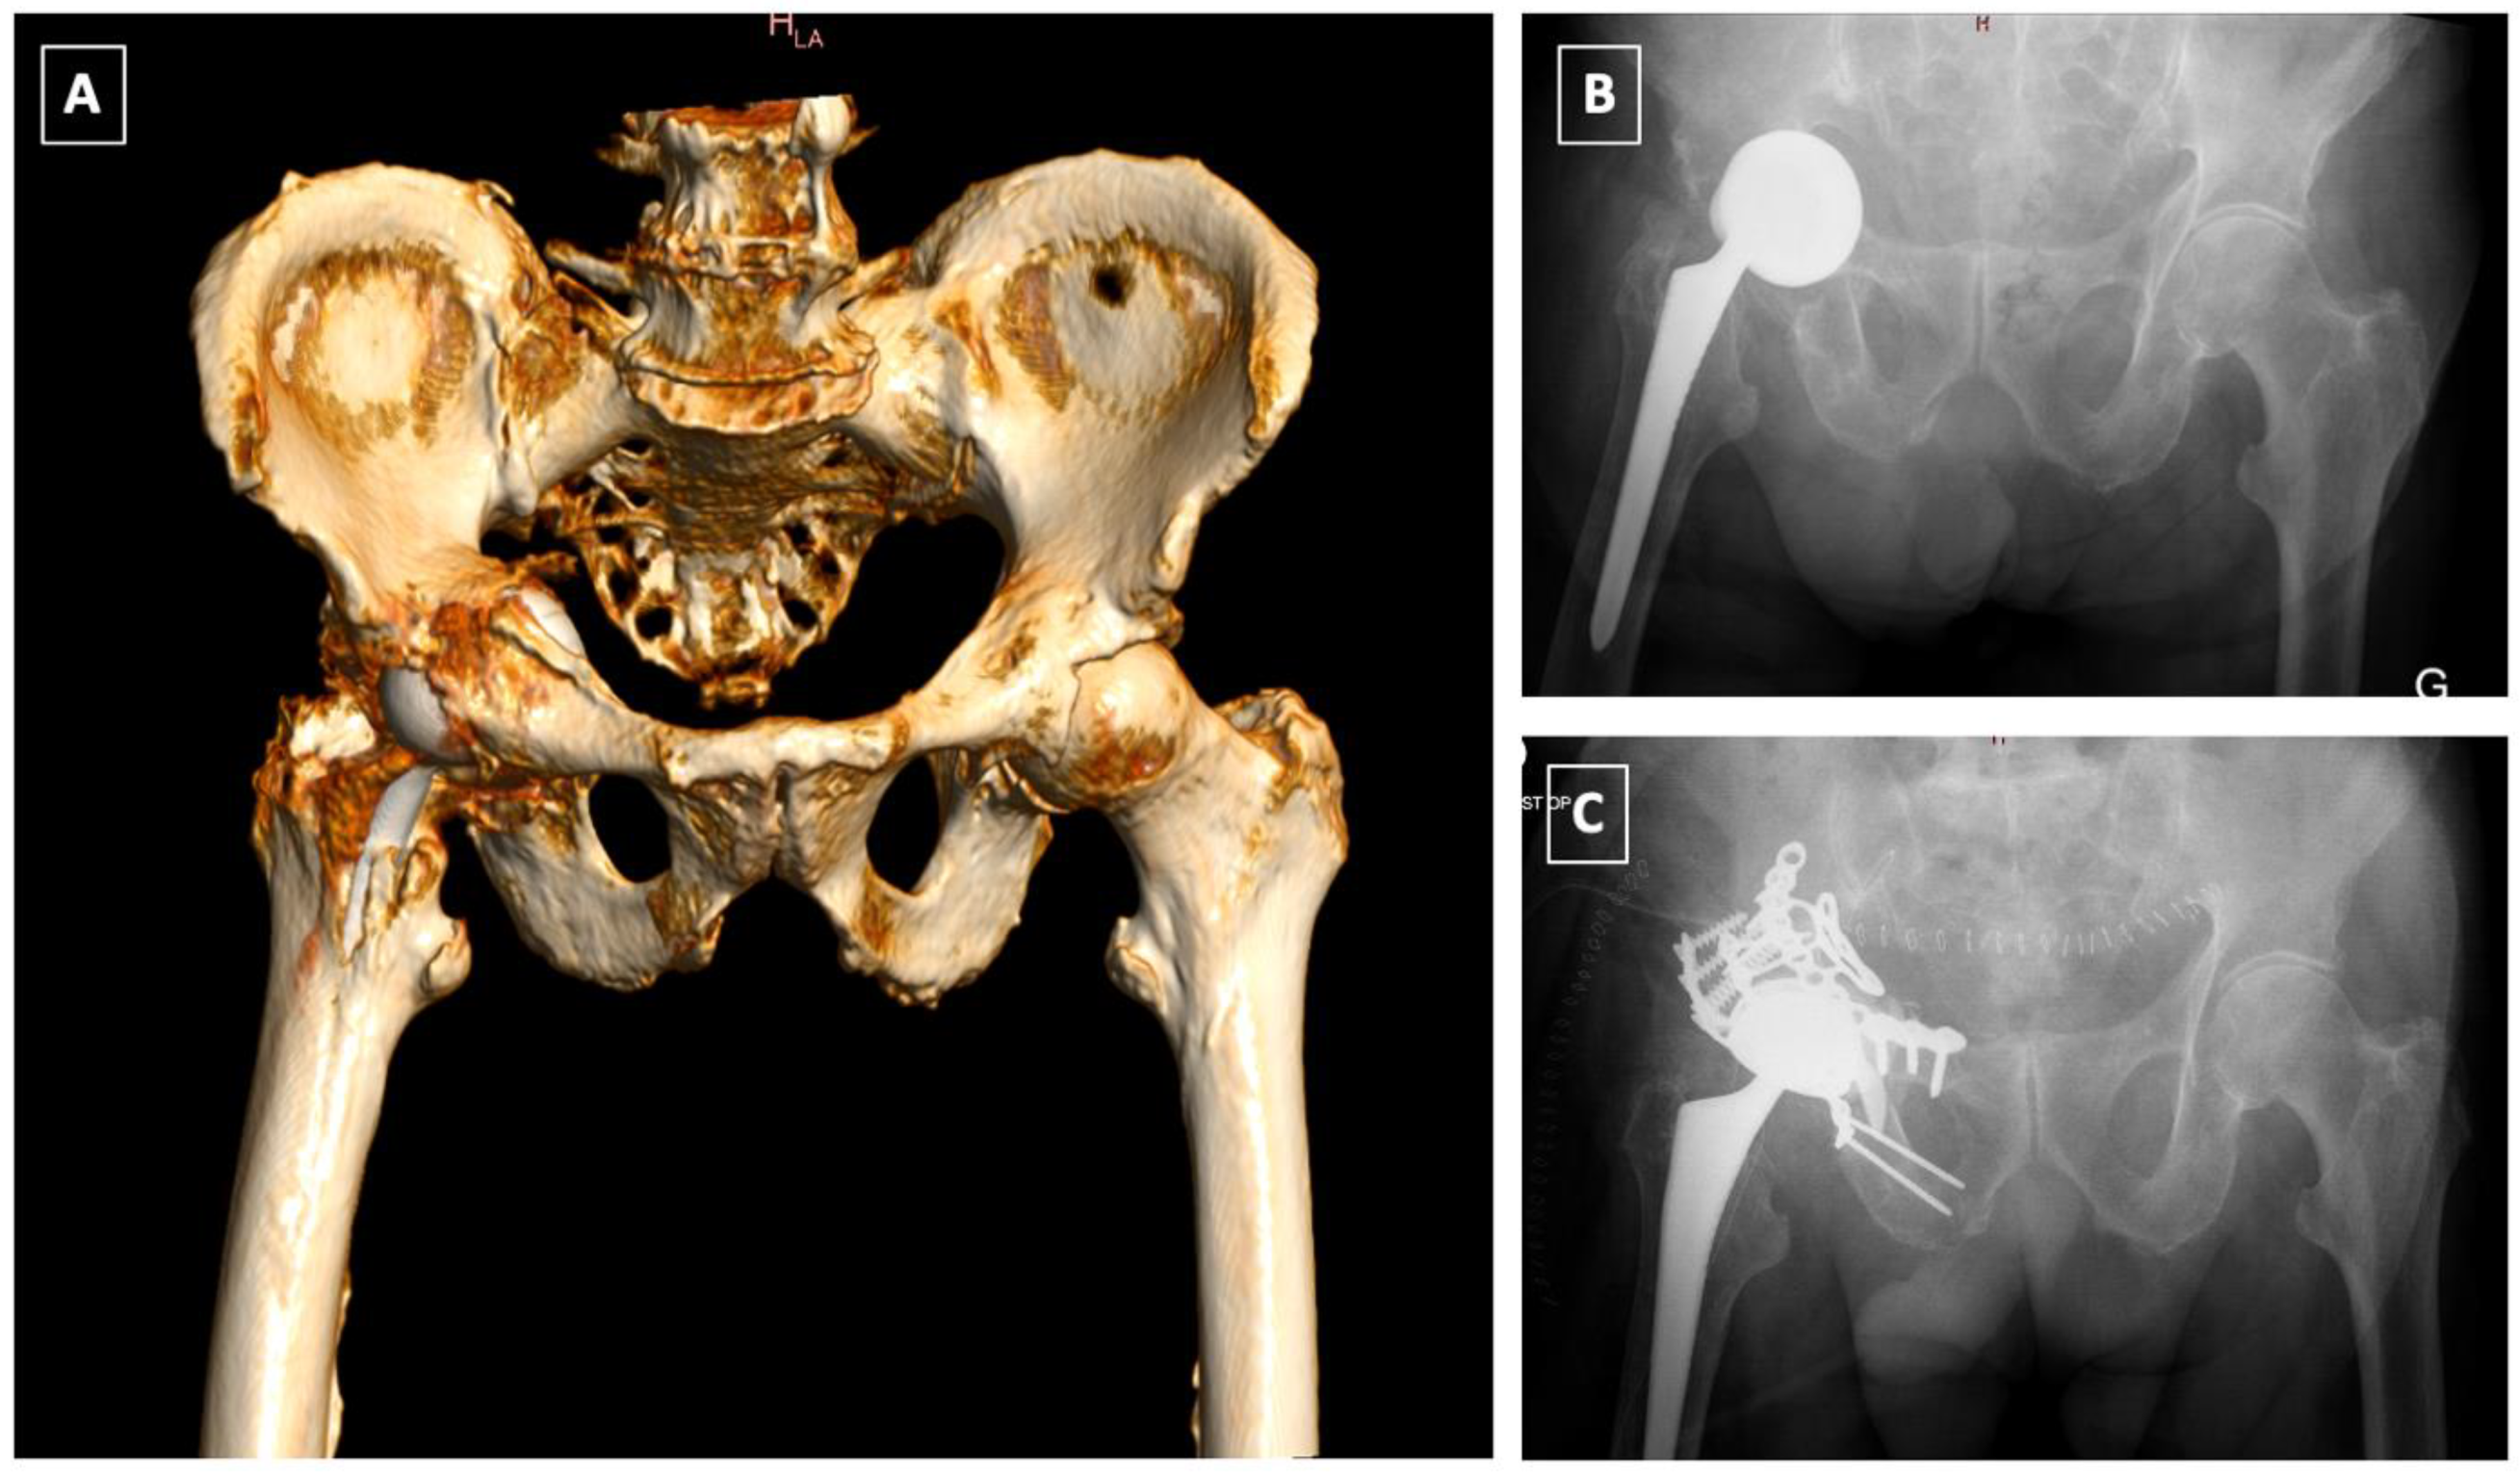

- Acetabular distraction was first described by Sporer et al. in 2012 [53]. The acetabulum is reamed until the antero-superior and postero-inferior margins are engaged. Remaining bone defects are filed with porous tantalum augments. An acetabular component of the same material, 6–8 mm larger than the last reamer is then impacted. The distraction creates a press fit and a pelvic recoil as a result of ligamentotaxis [54]. The latter in conjunction with multiple screws inserted in the remaining ilium and ischium provides initial stability. The polyethylene liner or a dual mobility cup is then cemented into the shell [53]. Although relatively new, acetabular distraction is a promising treatment for chronic PD. Excellent results [40,42,53,55], with low complication rates, 3–5% aseptic loosening [40,53], have been reported at 2- to 7-year follow-up.

- Custom-made triflange implants are another option to address chronic PD with severe bone loss. Based on a preoperative CT scan, an individually produced titanium, porous and/or hydroxyapatatite-coated triflange cup is made. Through the fixation of the three flanges (ilial, ischial and pubic), initial stability with the hip COR in anatomic position can be achieved. Excellent results and >80% survivorship of the implants are reported [42,56,57,58]. The disadvantages of this implant are high costs, long manufacture time (6 weeks) and the high rates of dislocation, up to 21% [42,56,57].